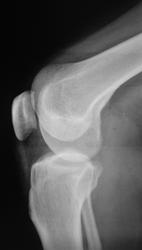

Травма. Пациент направлен на рентгенографию коленного сустава.

Пациент направлен на рентгенографию коленного сустава.

Определяется уплотнение кортикального слоя суставных поверхностей, заострение межмыщелковых возвышении, слабовыраженная краевая  костная деформация - по совокупности   тянет на ДОА I ст. Ну, а то, что на прицельной то это - игра теней - мое мнение.

Прицельных снимков не делали, это обычных два снимка на цифре.

ДФА 1

артроз пателло-феморального суставчика и лигаментоз крестовидных связок.